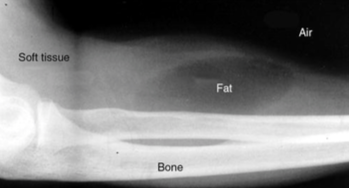

What are the 4 basic densities on an x-ray?